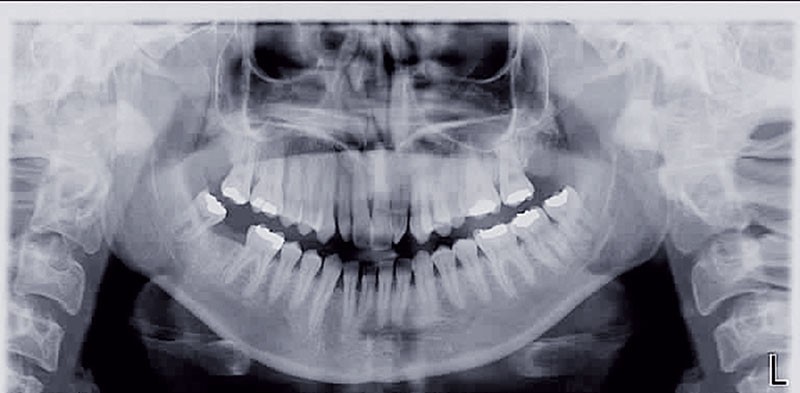

Cette patiente est venue consulter pour son occlusion inversée et ses importantes malpositions dentaires antérieures associées à la perte d’une dent et à des problèmes parodontaux.

• Malocclusion de classe III d’Angle par rétroalvéolie maxillaire,

• endoalvéolie maxillaire avec occlusion inversée antérieure et bilatérale,

• infraclusion incisive,

• fortes malpositions des incisives supérieures (dont 22 qui est en rotation axiale disto-palatine de 90°), • dysharmonie dento-dentaire (12 en « grain de riz » est aussi en rotation marginale disto-palatine de 45°),

• anomalie de la forme d’arcade maxillaire, 47, 18 et 28 sont absentes. (fig. 1 à 8), 48 est positionnée très postérieurement, quasiment au niveau de la branche montante (fig. 9 et 11).